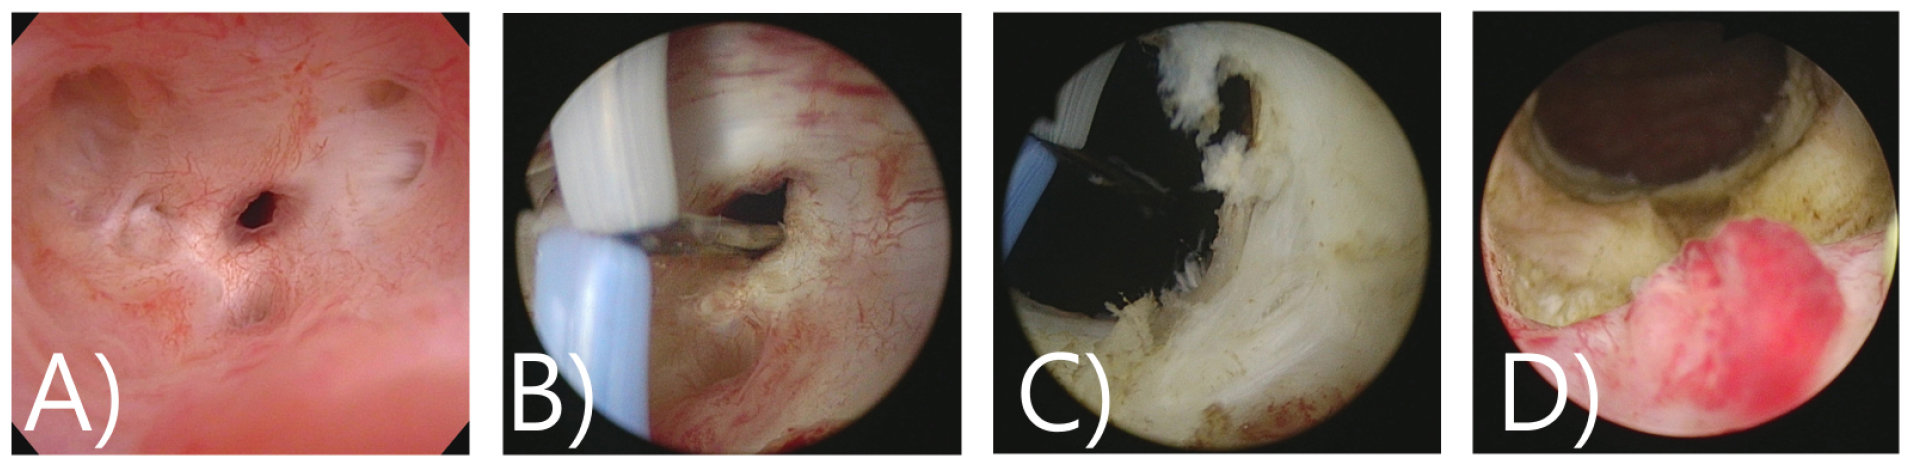

그림 7.

수술과정: A)~D); Deep incisions at 6 o’clock using a cold knife without the use of intralesional injections following 3, 6, 9, 12 o’clock multiple deep incision. An optical urethrotome was used to incise the dense bladder neck scar and open up the channel. E) Additional reTUR of remnant bilateral prostate with TUR bipolar vaporization loop (only use pure cutting current) F) cold knife